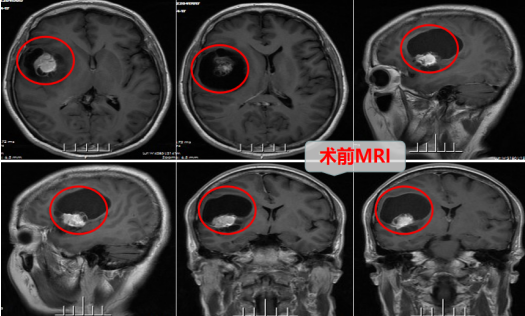

朱女士近一周无端反复地出现头晕甚至有天旋地转的感觉,而且肢体时不时有麻木无力,就诊当地医院检查后,居然发现是脑子里长了肿瘤!更为恐怖的是,由于该肿瘤位置紧靠重要脑功能区(右侧中央区及岛叶),肿瘤必须做手术,但医生说手术后发生瘫痪、认知障碍等风险极大。为得到好的治疗,减少手术并发症、后遗症的风险,家人带着她来到广州抗癌协会神经肿瘤主委单位—广东三九脑科医院神经外十科。

在完善了相关的术前准备后,神经外十科团队在广州抗癌协会神经肿瘤主任委员欧阳辉教授带领下为朱女士实施了精准的右侧额岛叶占位病变(胶质瘤)切除术。手术要全切除肿瘤而又不引起脑正常结构和功能的破坏,对于神经外科医师来说仍然是一个挑战。 朱女士这次手术治疗的难点在于:岛叶肿瘤深埋在额颞叶深部,而且侧裂中及岛叶表面行走的是大脑半球主要的供血动脉—大脑中动脉及其分支,多根细小的穿支动脉(豆纹动脉)供应内囊及基底节,如果这些血管一旦被破坏,必定会引起对侧肢体偏瘫的严重后果,即便保留了血管主干,这种操作也可能使大脑中动脉术后发生痉挛,引起脑缺血导致术后神经功能缺损,这就要求术者在制定手术计划以及在手术操作中都特别重视,做到心中有数;在打开外侧裂和切除肿瘤时,需要术者剑胆琴心,如履薄冰、如临深渊,精细地分离血管,雕刻式地切除肿瘤,而且不适当的牵拉额叶也可能引起运动和语言功能障碍,这就要求术者在少牵拉或无牵拉下操作。总之,这类手术医生要求医生既有丰富的临床经验、娴熟的显微神经外科技术,还要非常有耐心和耐力。

术中,医生团队利用神经导航、荧光显影等先进技术,在高清智能显微镜放大下,仔细精准地操作,小心分离并逐渐安全切肿瘤,术中出血很少,成功安全切除了肿瘤。术后朱女士神志清醒,因术中脑组织及周围血管保护良好,术后第三天朱女士可下床少量活动,能自行康复锻炼,无癫痫发作,无构音障碍,无肢体无力、感觉障碍等,恢复良好。